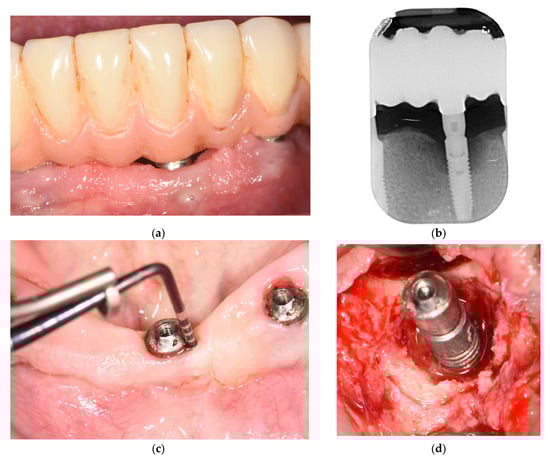

2. Materials and Methods

3. Results

- Bianchini, M.A.; Galarraga-Vinueza, M.E.; Bedoya, K.A.; Correa, B.B.; de Souza Magini, R.; Schwarz, F. Implantoplasty Enhancing Peri-implant Bone Stability Over a 3-Year Follow-up: A Case Series. Int. J. Periodontics Restor. Dent. 2020, 40, e1–e8. [Google Scholar] [CrossRef]

- Bianchini, M.A.; Galarraga-Vinueza, M.E.; Apaza-Bedoya, K.; De Souza, J.M.; Magini, R.; Schwarz, F. Two to six-year disease resolution and marginal bone stability rates of a modified resective-implantoplasty therapy in 32 peri-implantitis cases. Clin. Implant. Dent. Relat. Res. 2019, 21, 758–765. [Google Scholar] [CrossRef] [PubMed]

- Suh, J.J.; Simon, Z.; Jeon, Y.S.; Choi, B.G.; Kim, C.K. The use of implantoplasty and guided bone regeneration in the treatment of peri-implantitis: Two case reports. Implant Dent. 2003, 12, 277–282. [Google Scholar] [CrossRef] [PubMed]

- Austoni, C.; Azzola, F.; Cavalli, N.; Morandi, P.; Francetti, L. Implantoplasty associated with the regenerative treatment of peri-implantitis. Dent. Cadmos 2019, 87, 262–269. [Google Scholar] [CrossRef]